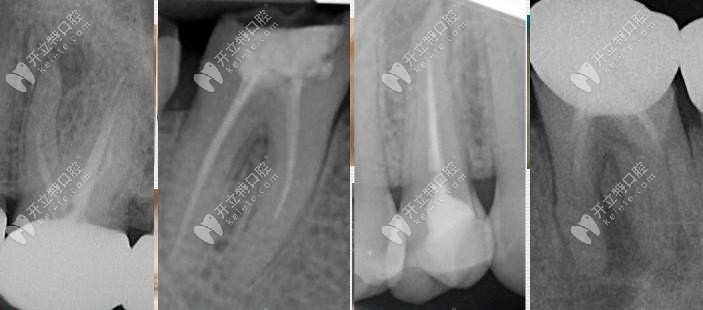

二次根管治療很麻煩,你一定要重視的根管治療失敗后的表現(xiàn)!

你是否也有寧愿拔牙也不做根管治療的想法呢?如果有的話,也是對的,畢竟根管治療上雖然可以保留部分牙根,對于醫(yī)生的操作要求也比較高。所以做根管治療后必要注意這幾大不成功表現(xiàn)。